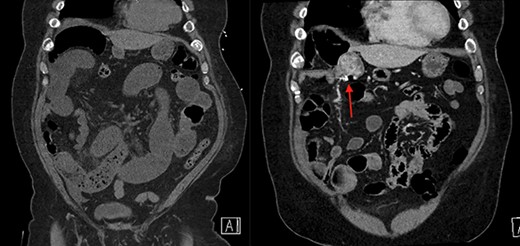

On the left is the initial CT scan non-contrast demonstrating dilated small bowel loops and a transition point in the right lower quadrant. On the right is the CT angiography (CTA), performed a week later, showing a mass and pill cam in the right upper quadrant.

On the left is the initial CT scan non-contrast demonstrating no obvious mass. On the left is the CTA, a week later, showing a mass and pill cam in the right upper quadrant.

The next week, unbeknownst to his Gastroenterologist about his recent small bowel obstruction admission, he then proceeded with a capsule endoscopy study to assess for other causes of his anemia. He tolerated the pre-operative bowel preparation without issues. After swallowing the capsule, he subsequently had bloody bowel movements. He then went to the ER and found to have a hemoglobin of 7.1, which was decreased from his prior week’s hospitalization, 8.4. A CT angiography (CTA) abdomen and pelvis was then performed that showed a 4 × 6 × 4.1 cm mass in the right upper quadrant with the capsule endoscopy at the level of the mass (Figs 1 and 2). The images from the capsule were unremarkable. On review of his imaging with radiology, it appeared that this mass was not apparent without IV contrast on his previous CT scan a week prior. In addition, a prior CT abdomen pelvis with IV contrast 10 months ago was negative for a small bowel mass. A repeat abdominal and pelvis CT with oral and IV contrast was done for confirmation. This re-demonstrated the 6 cm mass with the capsule stuck proximal to it; therefore, we performed a diagnostic laparoscopy.

Surgery revealed a small bowel tumor in the jejunum (Figs 3 and 4), which was resected and intestines re-anastomosed. The capsule was not identified within the lumen of the resected segment and had traveled through the obstructed segment distally. He had an unremarkable recovery and sequential X-rays demonstrated passage of the capsule. The pathology revealed metastatic renal cell carcinoma with intraluminal mucosal ulceration, 0/6 lymph nodes positive. He did well post-operatively and was referred back to his oncologist for further evaluation of his cancer.